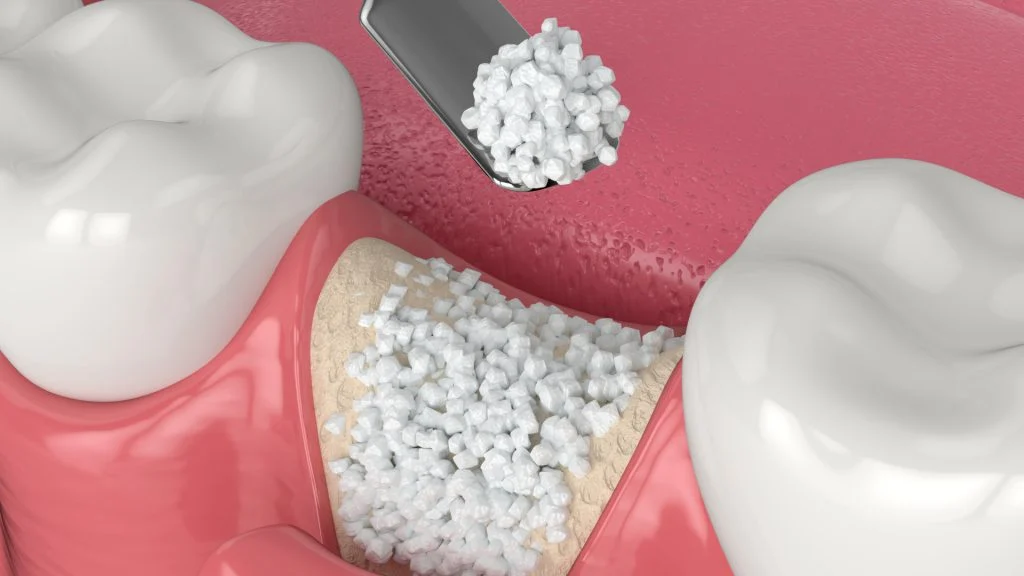

What Is Ridge Preservation?

- Performed immediately after a tooth extraction to prevent bone shrinkage.

- Fills the empty socket with bone graft material to maintain ridge shape and volume.

- Maintains implant eligibility by preventing collapse of the alveolar ridge.

- Commonly combined with collagen membranes to protect the area during healing.